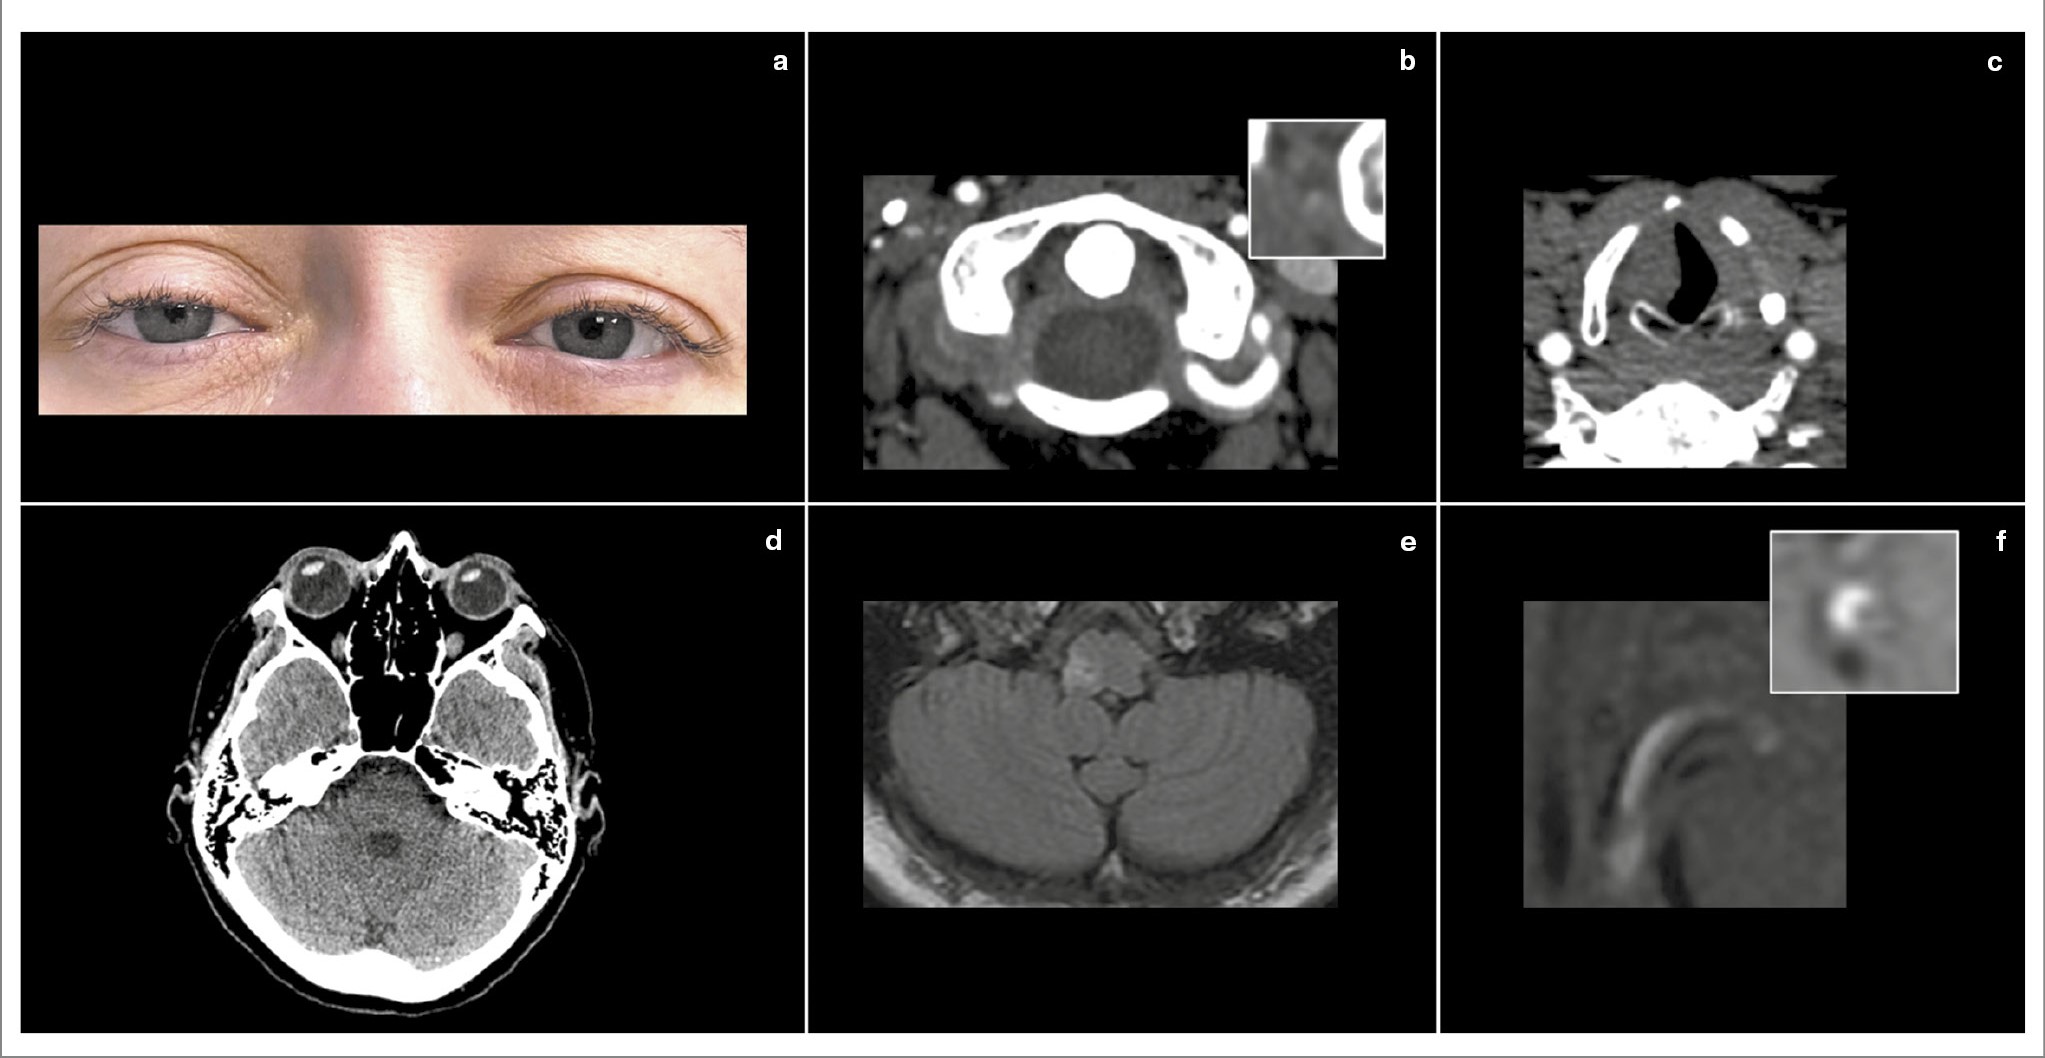

Редким вариантом ЛМИ является синдром Опальского (описан польским невропатологом Adam Opalski в 1946 г.), который характеризуется наличием ипсилатерального гемипареза, связанного с повреждением пирамидного тракта ниже перекреста пирамид [40] (рис. 5). Синдром необходимо отличать от синдрома Бабинского–Нажотта, при котором типичная картина ЛМИ сочетается с контралатеральным гемипарезом за счет вовлечения в очаг пирамидного тракта выше перекреста пирамид [41].

Рис. 5. Клинический пример синдрома Опальского. Пациент 51 года. Длительное время страдает артериальной гипертензией и сахарным диабетом 2-го типа, в 2018 г. перенес инфаркт миокарда. 2 декабря 2022 г. вечером почувствовал головокружение, шаткость при ходьбе. На следующий день появилась слабость в левой ноге. Поступил через сутки после возникновения первых симптомов. В неврологическом статусе при поступлении – интенсивный горизонтальный нистагм, направленный вправо, положительный OLD-тест слева, синдром Горнера слева (a, верхнее изображение), легкий левосторонний гемипарез (a, нижнее изображение), дизартрия и икота. Выполнена КТ головного мозга, визуализированы кальцификаты в проекции IV сегмента левой позвоночной артерии, а также выраженная содружественная девиация глаз влево (b). При проведении КТА выявлен выраженный стеноз IV сегмента правой позвоночной артерии (c), а также медиальное смещение левой голосовой связки, свидетельствующее о ее парезе (d). МРТ, выполненная на следующий день, позволила визуализировать инфаркт дорсолатеральных отделов продолговатого мозга слева, распространяющийся ниже перекреста пирамид (e). При введении контраста обнаружено его интенсивное концентрическое накопление стенкой IV сегмента левой позвоночной артерии, свидетельствующее о нестабильной субстенотической атероме (f).